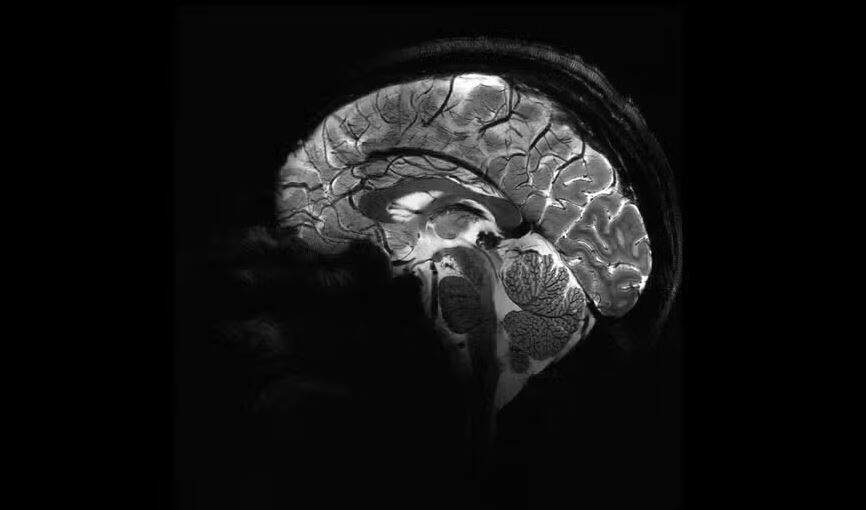

O cérebro dos homens “encolhe” 70% das 7h até às 20h e, então, reinicia, de acordo com um novo estudo. Esse processo foi associado a alterações nos hormônios esteroides, ou seja, testosterona, cortisol e estradiol, que ocorrem ao longo do dia no corpo masculino.

Para encontrar as evidências, os pesquisadores escanearam o cérebro de um homem de 26 anos 40 vezes no período de 30 dias. Os exames de ressonância magnética foram realizados às 7h e às 20h. Na manhã, o grupo de três hormônios estão em seu nível mais alto, enquanto à noite, estão no mais baixo.

A equipe de pesquisadores descobriu que as mudanças coincidem com a queda e o aumento dos hormônios esteroides. Então, quando os níveis aumentam, o cérebro muda seu volume. Por isso, o declínio deles foi ligado ao menor volume cerebral.

São afetadas a espessura do córtex (a camada mais externa do cérebro), especialmente os córtices occipital e parietal foram as que mais encolhem e a matéria cinzenta (composta pelos neurônios e as conexões entre eles), que perde 0,6% do seu tamanho original.

Além delas, outras regiões mais distantes do cérebro, como o cerebelo (responsável coordenação motora, o equilíbrio e o controle do tônus muscular), tronco cerebral (mensageiro entre cérebro e corpo) e partes do hipocampo (armazenamento de memórias), também apresentaram diferenças.